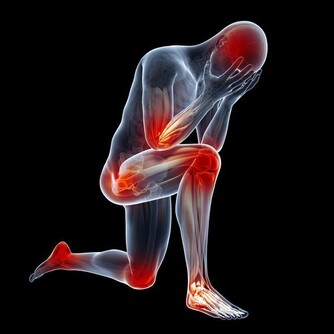

慢性型早期會出現煩躁、食慾減退、低熱、多汗、脫髮、以後有典型的骨痛症狀。

維生素D在所有維生素中是最容易使人中毒的一種,其中毒症狀和體徵主要有:高鈣血、肌無力、感情淡漠、頭痛、厭食、噁心、嘔吐、骨痛、異位性鈣化、蛋白尿、高血壓和心律失常等。慢性高鈣血可導致全身血管鈣化、腎臟鈣質沉著和迅速出現腎功能衰退。

維生素B1、K都有嚴重過敏反應甚至致死的報告,曾見過維生素B12發生過敏性休克。另一方面,不同的維生素各有其特異的不良反應,如維生素A可出現頭痛、煩躁、嗜睡等神經系統症狀;維生素D可引起動脈、腎曲小管用至骨骼的鈣化和過度鈣化;維生素E可引起血栓形成及月經過多等等。